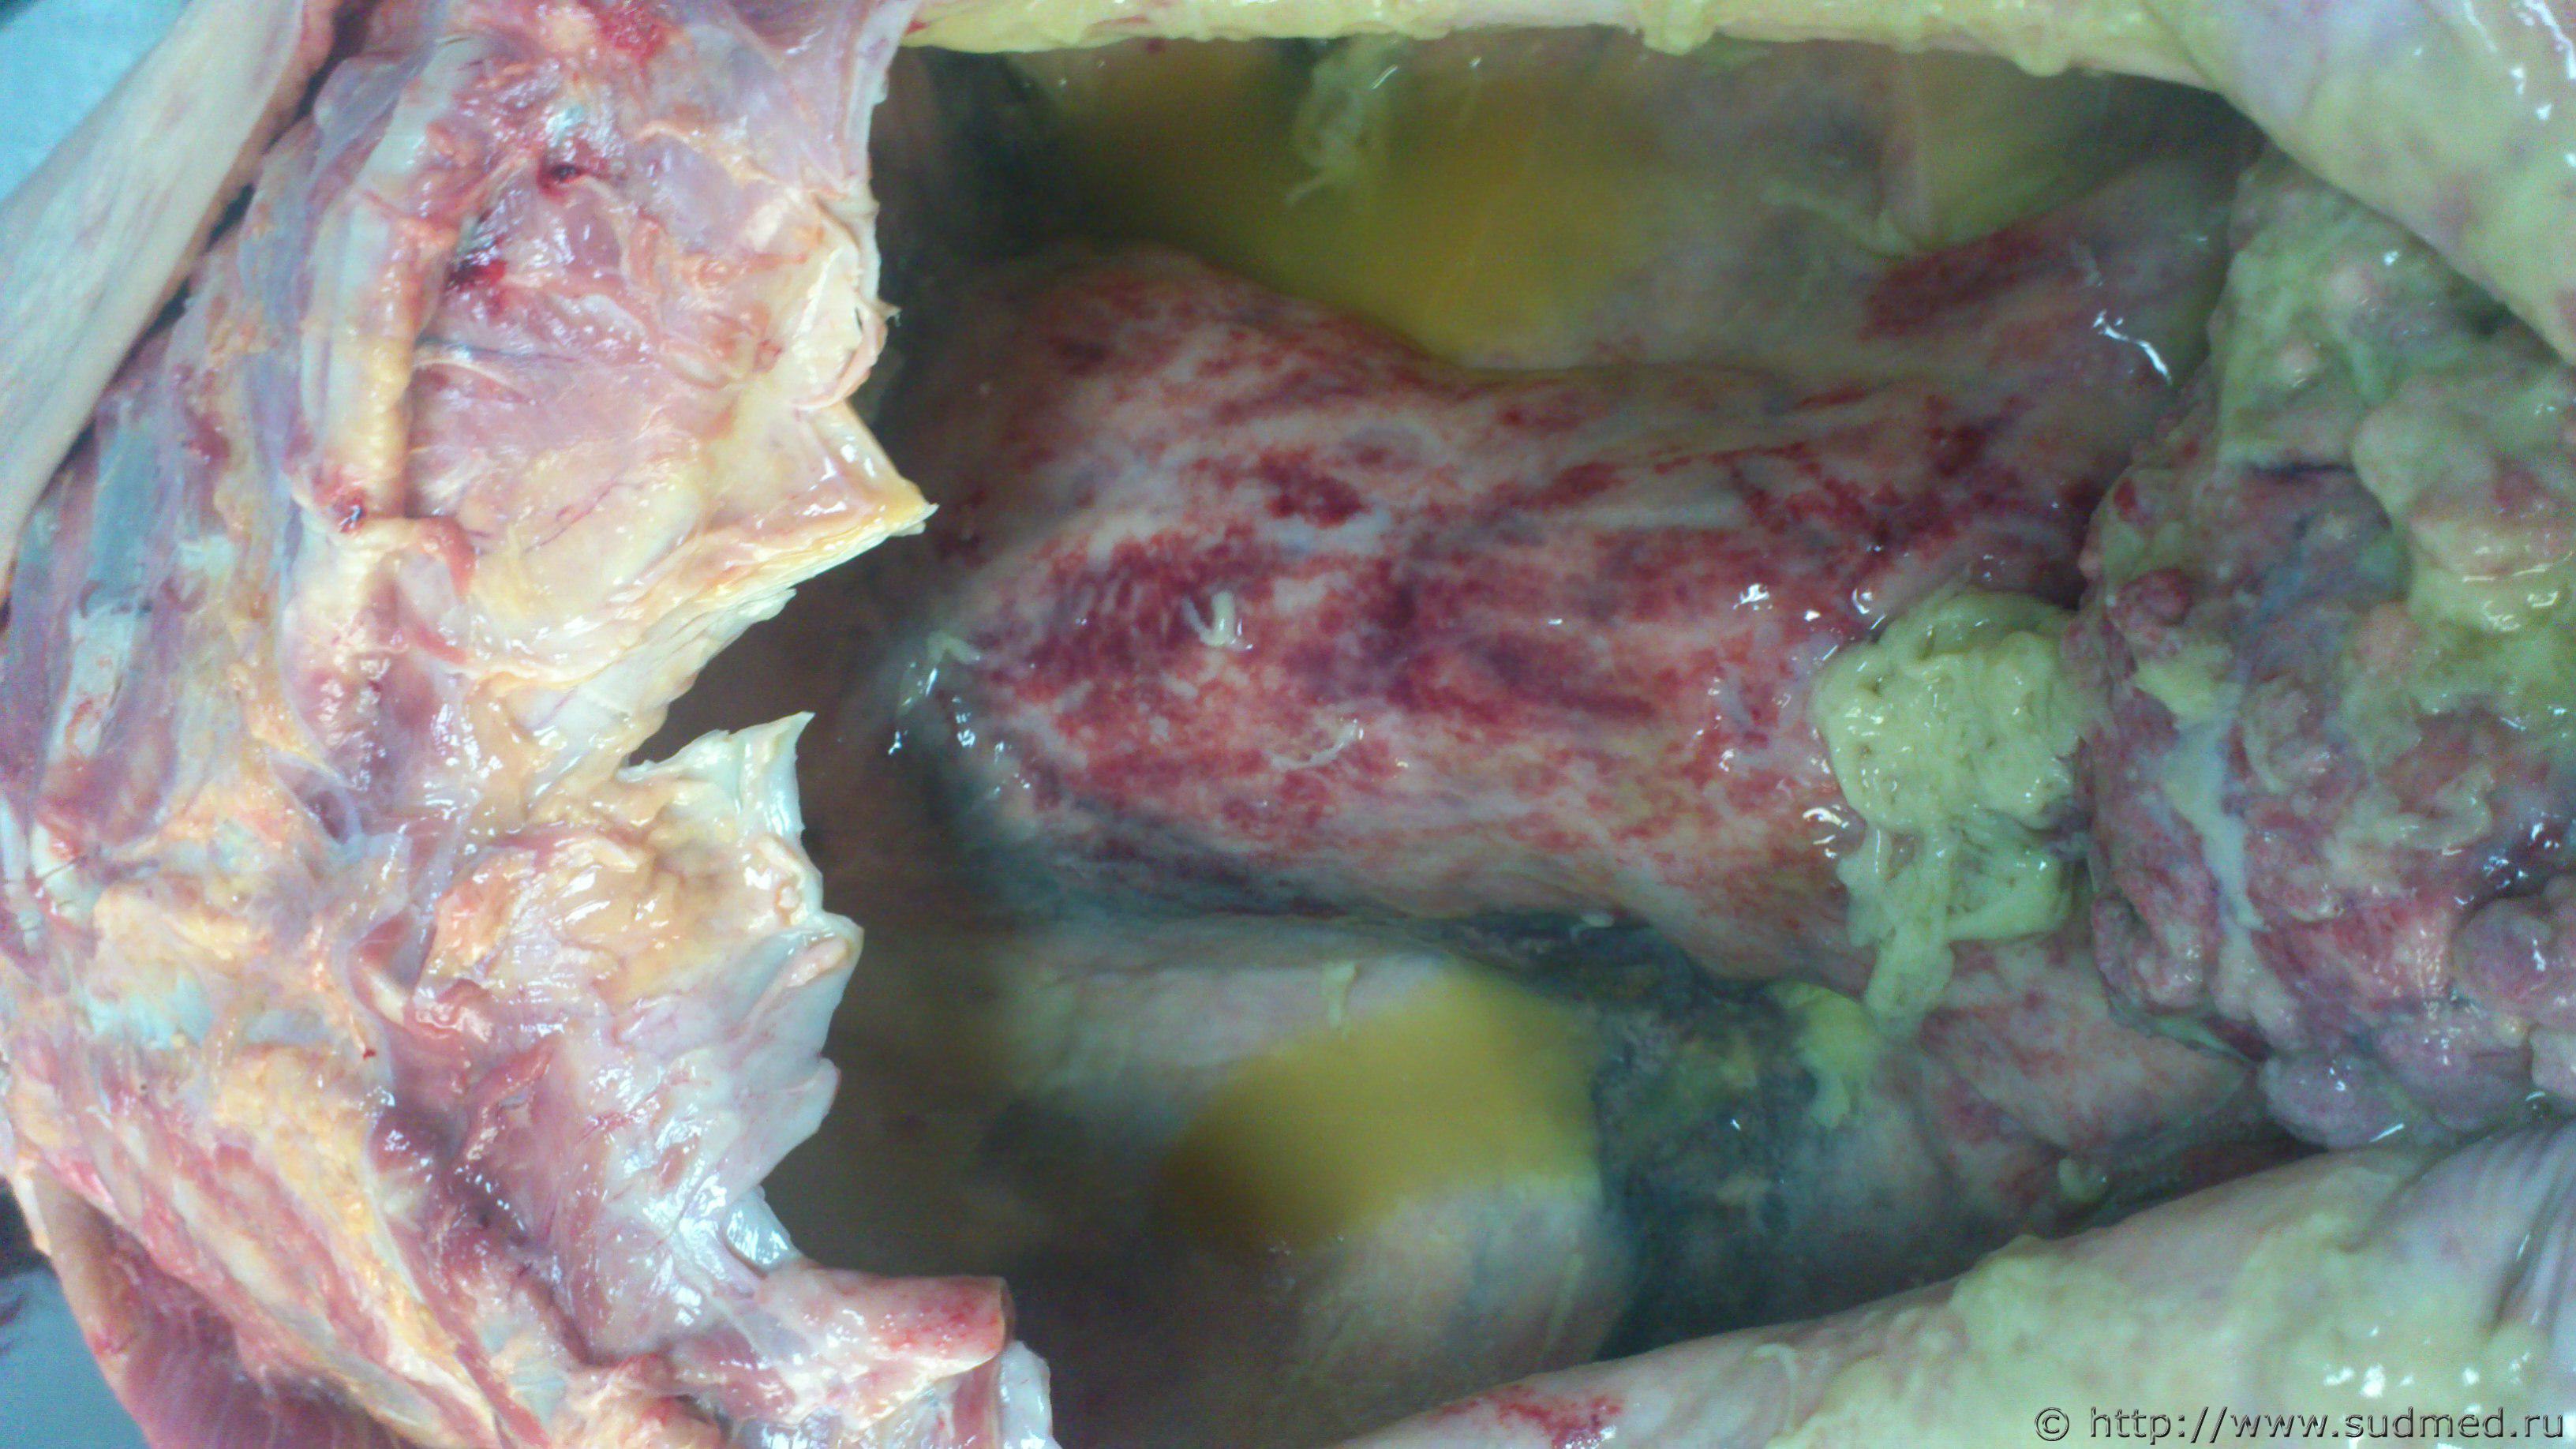

Интересный случай вышел autopsy.gif .

Вскрыл, а органов нет. При исследовании в брюшной полости около 6 литров жидкости, огромный с распадами и кистами рак яичника, а все органы припаяны к задней стенке брюшной полости спаячным, пластинчатым образованием.